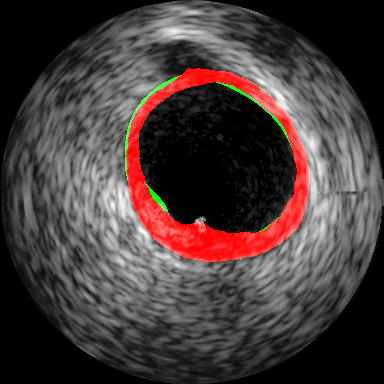

The architecture of the FCN used is illustrated in Fig. 2. It consists of an encoder unit, consisting of convolution and maxpooling layers and a decoder unit consisting of convolution and unpooling layers. The encoder resembles a VGG11 [5] barring the terminal classification layer. Feature maps are downsampled, and the number of features maps increases progressively with layer. The decoder is built to match activation map sizes in layers matched to depth in encoder with use of pooling index transferred for unpooling operation. This improves the boundary segmentation preserving conformity around small structures which is similar to the SegNet [4]. However, max pooling in encoder with a SegNet typically leads to the loss in subtle information related to smaller structures which progressively vanishes across successive depths. To address these limitations, we introduce the activation concatenation concept similar to that used in the UNet [6] which is of relevance to biomedical image segmentation tasks. We have employed ReLU [16] as an activation function in all layer except for the terminal layer of decoder where we have used sigmoid activation function [16] to force the output towards the [0,1] extremity. The network is trained with weighted binary cross-entropy (WCE) [16] loss function. Weights are calculated using a morphological distance transform giving higher weights to the pixels closer to the contour as illustrated for the IVUS in Fig. 3(c) and Fig. 3(j) for thyroid. The idea of using both maxpool indices and concatenating techniques helps in improving the preciseness of localization. The input is a grayscale image, and the first layer of the encoder provides an output with channel feature map to match input size expected in a VGG11.

Intravascular Ultrasound Segmentation: We have used IVUS data from the 2011 MICCAI workshop [8] which is composed of pullbacks of different patients acquired at MHz (Dataset B). The proposed method is compared with nine different methods, where eight approaches have been reported earlier in [10]. In Table 1, we have included only the best results among the participants (P1-P8) in [8]. Subsequently 2D visualization of segmented IVUS contours are presented in Fig. 3(d) - (g) and the lumen and external elastic luminae border segmentation in the whole pullback is visualized111Supplementary material. The proposed method outperforms the recent related prior art [11] as presented in Table 1.